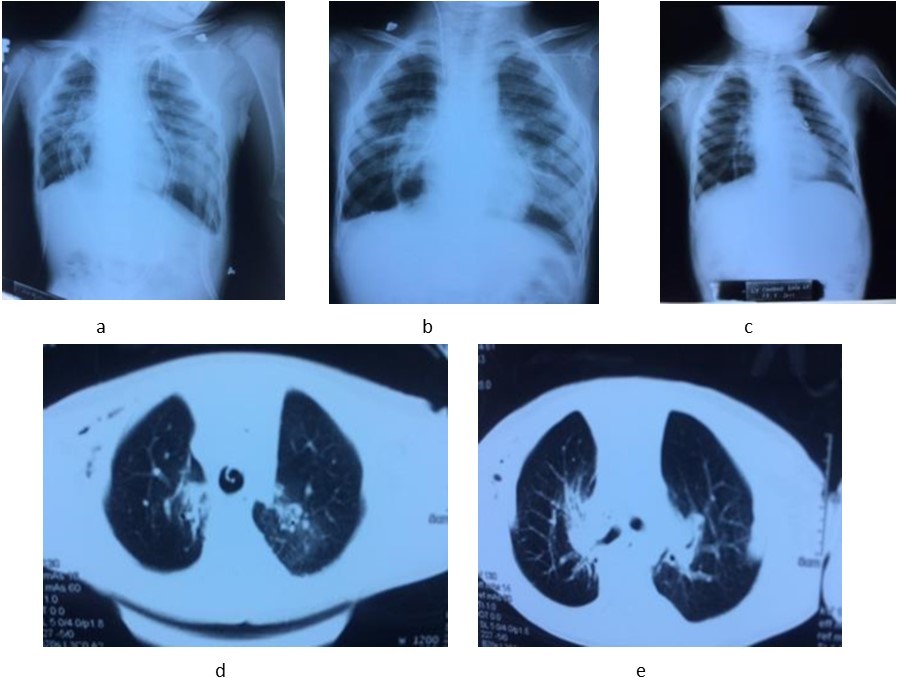

A 7 years old boy was diagnosed of difuse congenital bronchiectasis with chronic respiratory failure and cor pulmonale. At the age of 2 months, he had many respiratory infections. When he was 2 years old, respiratory infection became more frequently, he has been usually hospitalized due to uncontrolled recurent respiratory infection. His main complains were frequent cough with sputum and shortness of breath. On September 2016 patient hospitalized with fever, cough with sputum purulence, severe dyspnea (mMRC of 4 points), cyanosis, difuse crackles in the both lungs, and severe malnutrition (height: 90 cm, weight: 11 kg, BMI: 13.5). The subclinical tests: PaO2: 77 mmHg, PaCO2: 46 mmHg, pH 7.46, SaO2 95% and HCO3-26.7mmol/l. CT-scan: severe difuse bronchiectasis; ECG: sinus tachycardia, right atrial hypertrophy; echocardiography: right ventricle enlargment, pulmonary arterial hypertension (47 mmHg). Blood group: O (+), Rh (D) (+); HLA class I: A02; A24; B13, B52; HLA class II: DRB1 01; DRB1 14. (Image 1)

Image 1.The chest CT-scan image of receipient (difuse bronchiectasis)

The chest CT-scan image of receipient (difuse bronchiectasis)